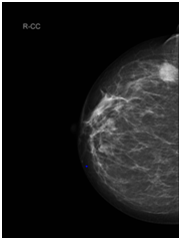

Staging CT chest & abdomen, showed bilateral lung nodules and numerous subcutaneous nodules, the largest seen in the umbilical area (Figure 4). Histology of the right breast biopsy reported staining for Melan-A & HMB45 is positive (Figures 5A‒5D). No staining for Cam5.2, ER, PR, CK7 and CK20. Ki67 is 10%. Appearances and immuno-profile are consistent with metastatic malignant melanoma. Due to disease dissemination, the patient has been referred to palliative oncological treatment.

Figure 5(C) x10 sheets of melanocytes positive for HMB45. Normal breast lobules at 12 o’clock do not stain for HMB45.

Figure 5(D) x40 sheets of melanocytes on the left are positive for Mel A. Normal breast lobules on the right do not stain for Mel A.

The case presented in this paper is of a wide spread disease, diagnosed initially from breast lesion biopsy. The sample was positive for Melan-A [melanoma antigen can be found on the surface of melanoma cells].

Also was positive for HMB45, which is a monoclonal antibody that reacts against an antigen present in melanomas. The specific antigen recognized by HMB-45 is now known as Pmel-17. No staining was detected for estrogens and progesterone receptors. It was negative for CK7 & CK20 which are characteristic markers for the glandular epithelia. Also was negative for Cam5.2 which is, anti-Cytokeratin stains most epithelial-derived tissue, including liver, renal tubular epithelium, and hepatocellular and renal cell carcinomas.